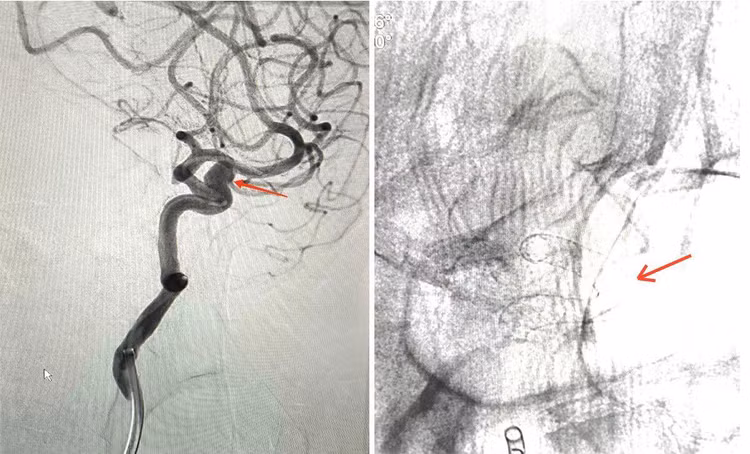

| Mạch máu não trước & sau can thiệp. Sau khi đặt stent nở tốt, đúng vị trí - Ảnh BVCC |

Ca can thiệp nội mạch cho người bệnh N.T.H thành công không có biến chứng trong và sau can thiệp. Sau khi đặt stent chuyển dòng, người bệnh vẫn có thể hoạt động và đi lại bình thường, có thể xuất viện sau vài ngày.

Sau khi được tư vấn phình mạch não sẽ vỡ bất kỳ khi nào và mức độ nguy hiểm khi túi phình vỡ sẽ để lại các di chứng rất nặng nề, thậm chí tử vong. Người bệnh đã được các Bác sĩ của Trung tâm đột quỵ thực hiện can thiệp đặt stent chuyển dòng mạch não, thời gian can thiệp chỉ khoảng 2 giờ. Ngay sau khi đặt xong stent, dòng máu đi vào trong lòng túi phình giảm hẳn, đã được kiểm soát và nguy cơ vỡ túi phình cũng giảm theo

Bác sĩ Phan Ngọc Nhu Trưởng khoa điều trị Thần kinh Đột quỵ bán cấp trực tiếp can thiệp cho người bệnh giải thích: “Khi máu không đi vào túi phình nữa thì dần dần túi phình này sẽ hình thành huyết khối bên trong, sau một thời gian túi phình sẽ mất hoàn toàn. Về lâu dài, tế bào nội mô bò lên trên stent, hình thành một lớp nội mạch mới”.